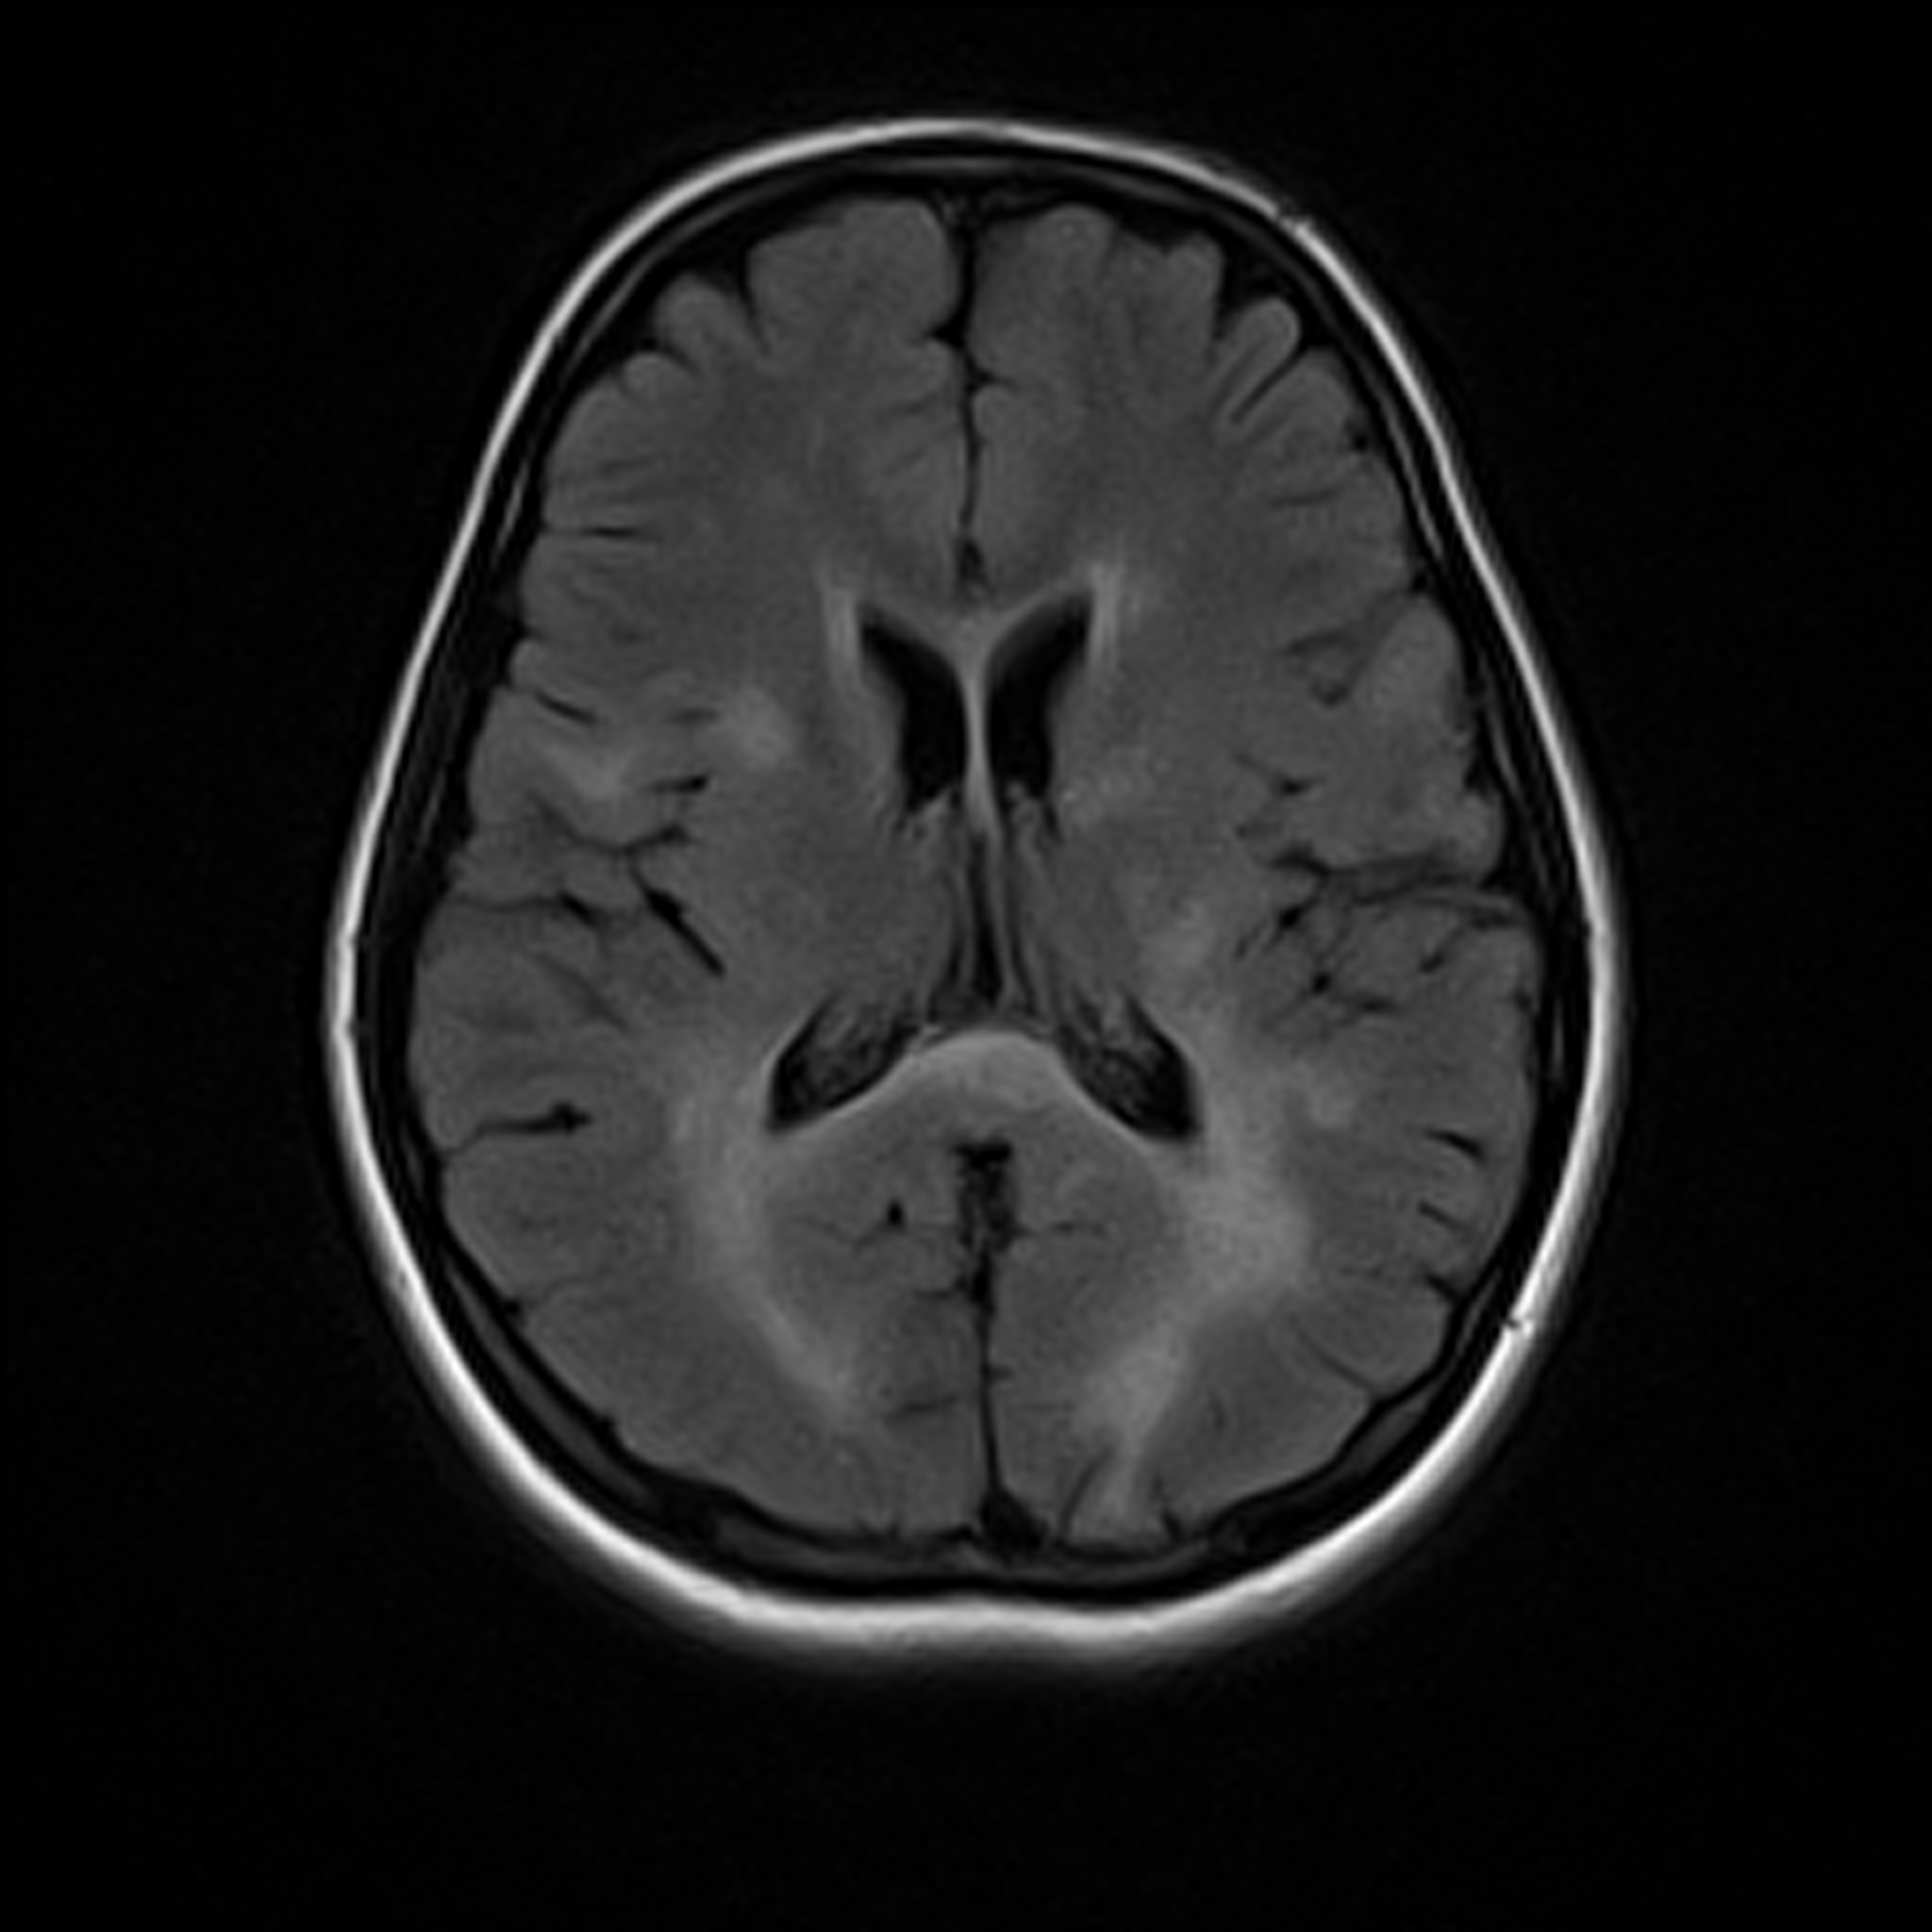

MRI

FLAIR

Segmentation

Multiple Sclerosis

MS Lesion Segmentation: AI-Powered Multi-Class Lesion Mapping in MRI.